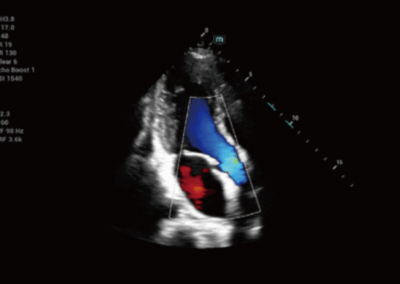

Consona N6

El Consona presenta soluciones nuevas y concretas, que lo ayudarán a realizar diagnósticos fluidos para amplios tipos de pacientes de manera eficaz.

No importa que su rutina sea en hospitales, clínicas, o que esté perfeccionando sus habilidades, en esta serie encontrará herramientas muy potentes y disponibles para mantenerse a la vanguardia.

Consona N7

El Consona presenta soluciones nuevas y concretas, que lo ayudarán a realizar diagnósticos fluidos para amplios tipos de pacientes de manera eficaz.

No importa que su rutina sea en hospitales, clínicas, o que esté perfeccionando sus habilidades, en esta serie encontrará herramientas muy potentes y disponibles para mantenerse a la vanguardia.

Consona N9

El Consona presenta soluciones nuevas y concretas, que lo ayudarán a realizar diagnósticos fluidos para amplios tipos de pacientes de manera eficaz.

No importa que su rutina sea en hospitales, clínicas, o que esté perfeccionando sus habilidades, en esta serie encontrará herramientas muy potentes y disponibles para mantenerse a la vanguardia.

RESONA i9

Resona I9 es un sistema de ecografía de aplicación general con características notablemente innovadoras. Estas innovaciones se desarrollan sobre la base de conocimientos profundos en situaciones clínicas complejas, para proporcionar respuestas precisas y oportunas, una gran eficiencia y una notable experiencia de usuario.

Se puede ajustar para utlizar mejor el espacio

Satisface fácilmente las distintas necesidades de exploración

- Diseño del panel de control inteligente y específico para exámenes clínicos con teclas especiales de tinta electrónica

- Diseño innovador y adaptable para diferentes situaciones clínicas